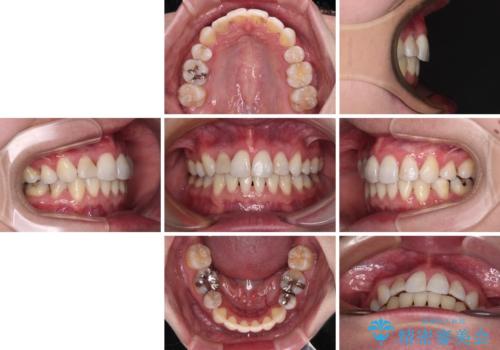

治療期間の目安は3年~3年半でしたが、咬み合わせにより上顎のスペースがなかかな閉じきらず、治療期間が長期化してしまいました。

期間はかかったものの、口元の張り出し感や歯のデコボコが解消され、患者様には大変満足していただけました。